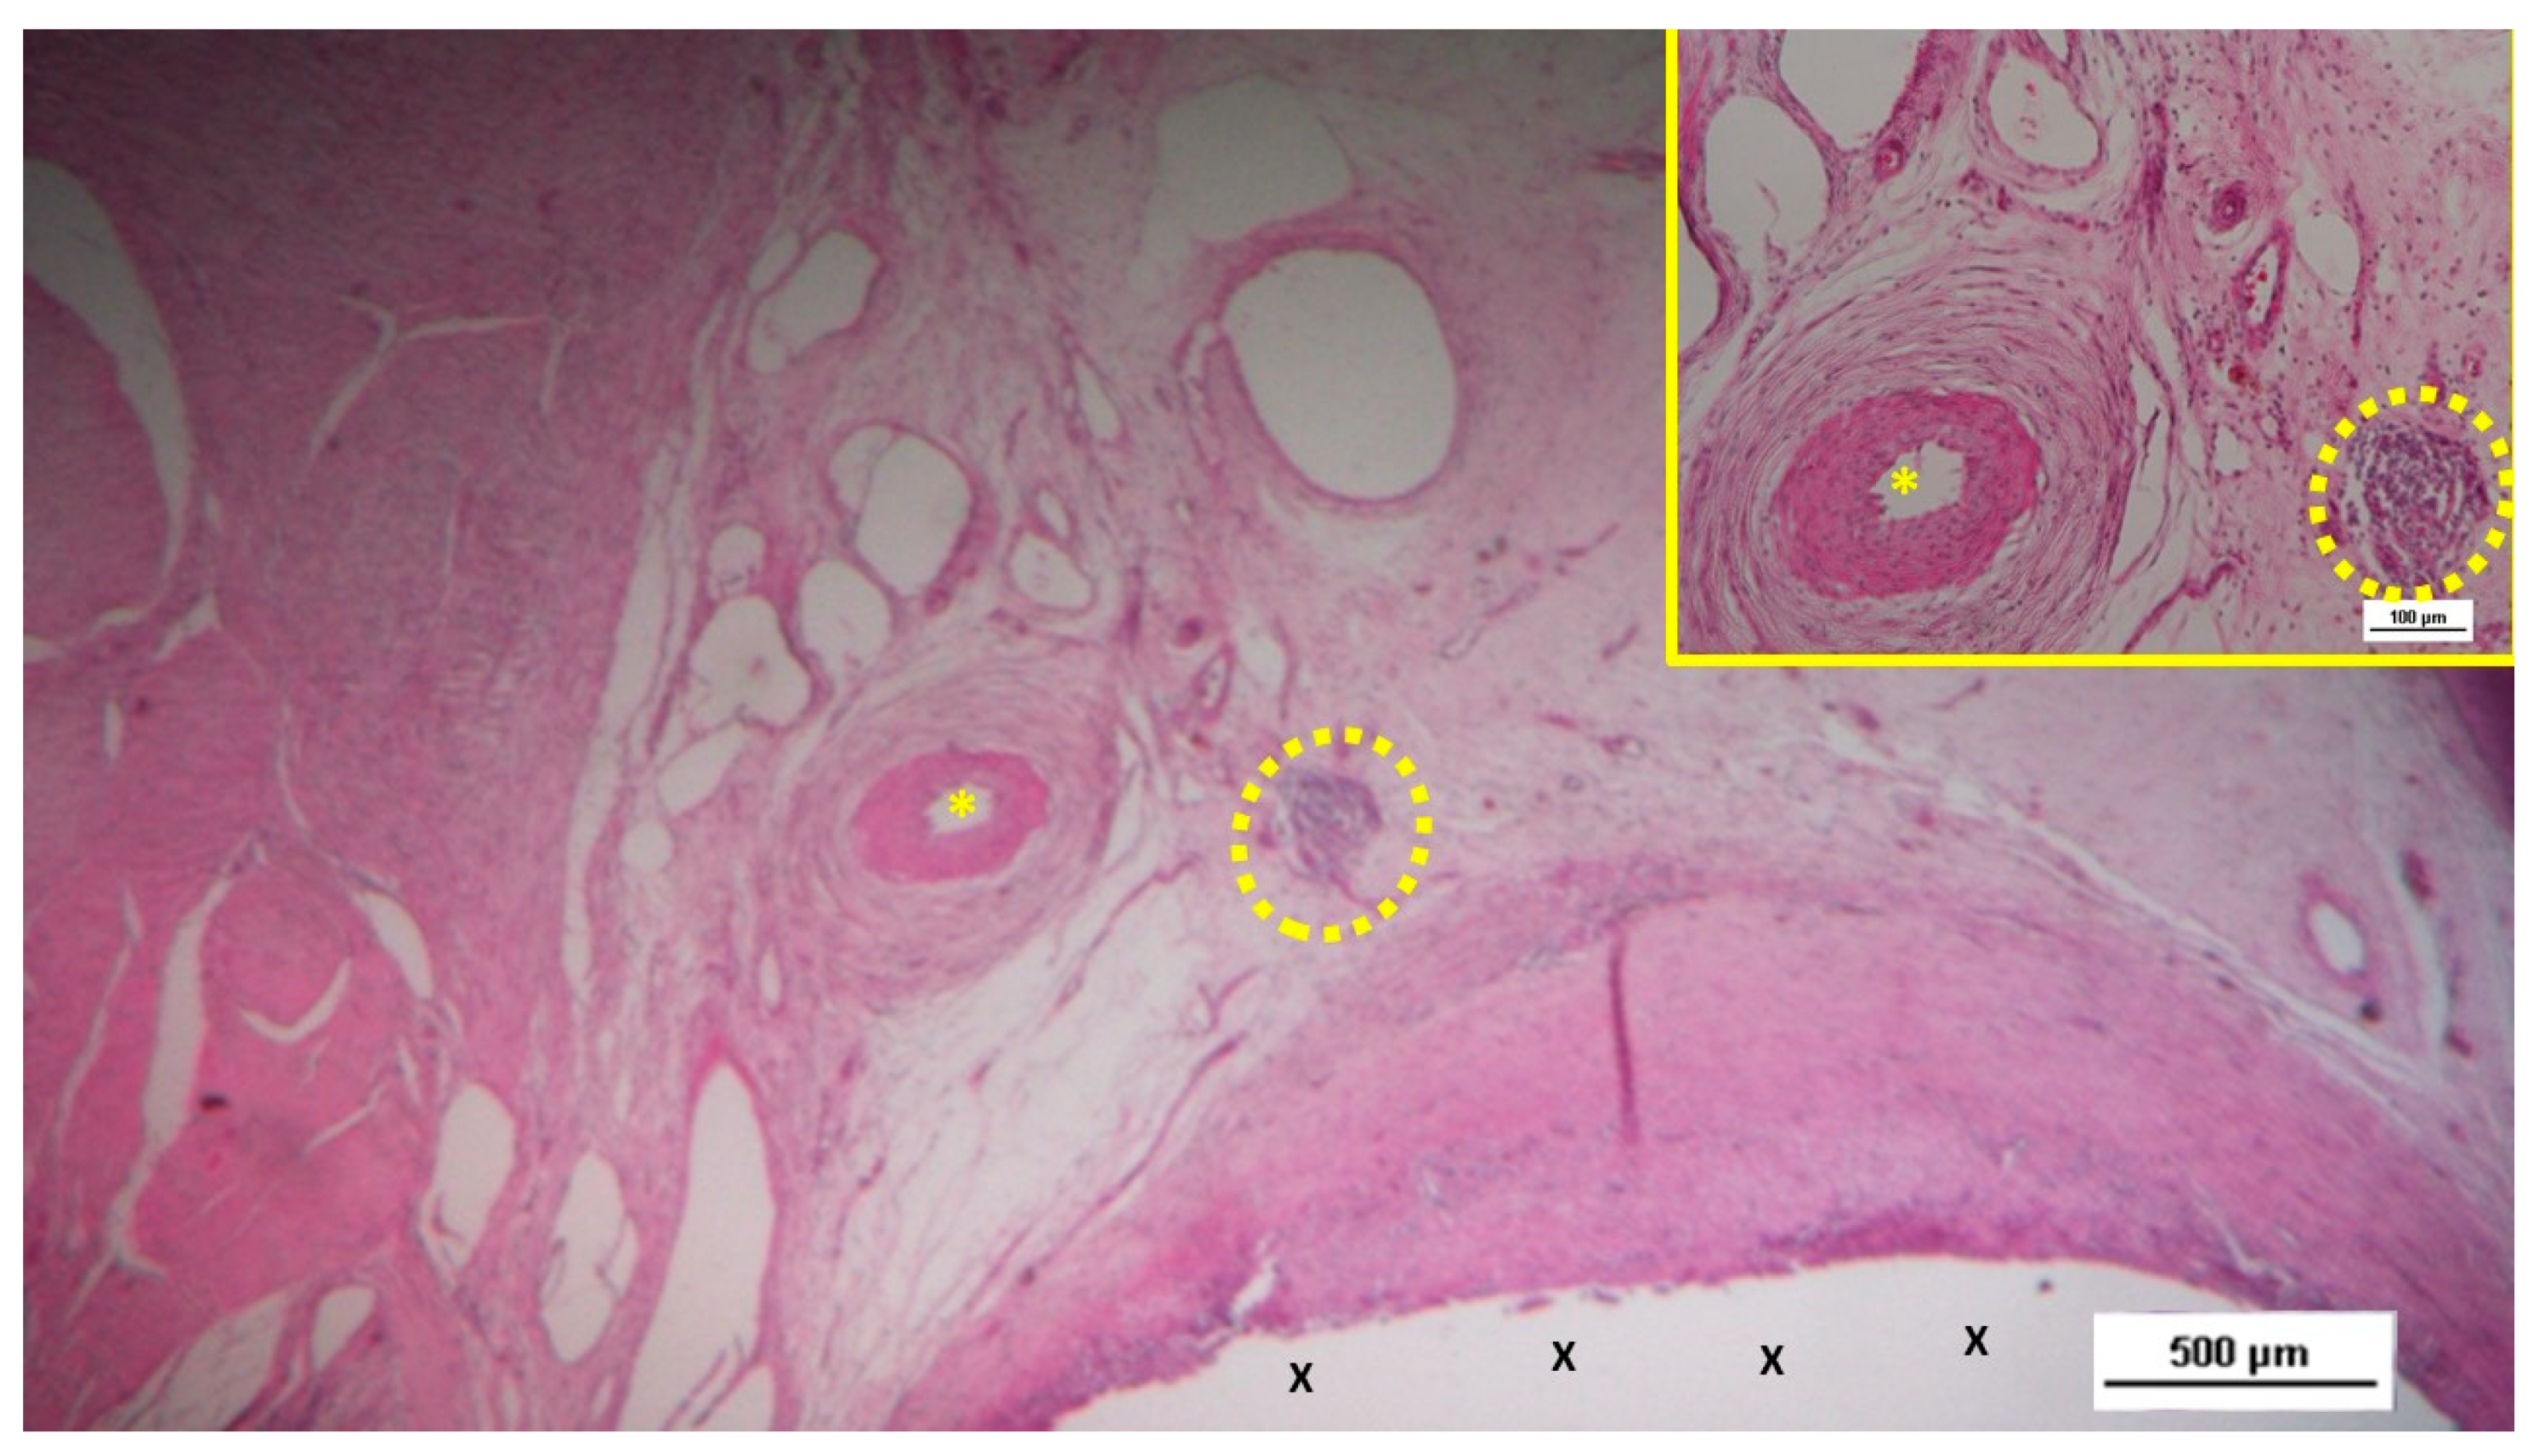

6-8 months post-implantation (long-term stage), there was a complete absence of inflammation, and the newly formed arteries and veins demonstrated full structural maturation across all components (Figure 11, Figure 12, Figure 13, Figure 14 & Figure 15).

In the short term, the histological analysis revealed the presence of immature vascular structures, indicative of early-stage angiogenesis. By the mid-term, a more extensive and organized vascular network had formed, with ongoing vascular development occurring inside the structure of the S&S device. In the long-term phase, the study observed the continued maturation of these vascular elements, which paralleled the development of other tissue components, particularly muscle fibers and nerves. By this stage, the muscular layer of the arterial and venous walls had fully matured, demonstrating the establishment of a competent vascular network capable of sustaining the newly formed, sophisticated tissues within the scaffold. In this final phase of vascular development, all vessel elements—arteries, veins, and capillaries—exhibited the structural characteristics of fully matured vessels. This well-established vascular network ensures adequate blood supply to the newly formed tissues, particularly muscle and nerve tissues, within the S&S device. All these evidences have been confirmed in detail by the statistical assessment.

Figure 14. Biopsy sample excised six months post-implantation from the 3D scaffold of the S&S device. The microphotograph shows multiple arterial structures (targeted elements) and veins (white spots) within a slack connective matrix, situated between two areas of muscle tissue (red-stained). No inflammatory reaction is evident near the S&S device fabric (X). The inset (lower left corner) provides a magnified view of an artery, displaying all three mature layers with a blood-filled lumen (*). HE 25X (main image) and 100X (inset).